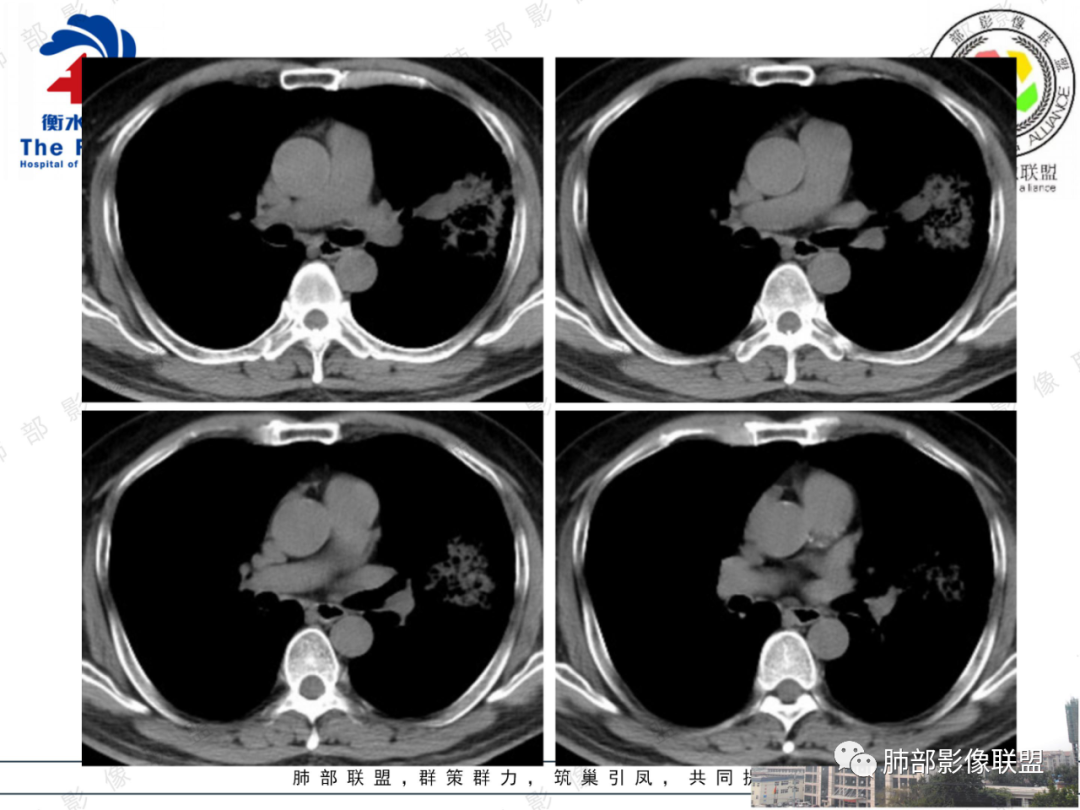

影像所见:左肺上叶尖后段团片状高密度影,边界清楚,其内密度不均,中心呈多发低密度影,与支气管关系显示不清。

治疗过程:抗感染治疗后间隔2月复查,胸片影像病灶稍增大。结合病史首先考虑恶性,肺炎型肺癌可能性大。鉴别肺克及毛霉?非结核分支杆菌肺病?

56岁男性,有糖尿病基础病。咳嗽咳痰2月,白细胞计数正常。培养出肺炎克雷白菌。胸部CT:左上肺空洞样病灶,厚壁,壁上多量小空泡样密度区,坏死区存留组织(感觉是假大空)。大部分边缘膀隆,部分可见分叶,部分边缘见小叶间隔阻挡;边缘见边界模糊的GGO,主要位于病灶以远处。抗感染治疗后病灶增大。考虑腺癌。

综上,左上肺假大空肿块伴周围实变,边缘似见粘液成分,胸膜牵拉凹陷,但收缩力偏弱,抗感染后两月复查,整个肿块增大,周围实变区增厚。符合腺癌(普通腺癌伴粘液分泌或粘液腺癌可能)